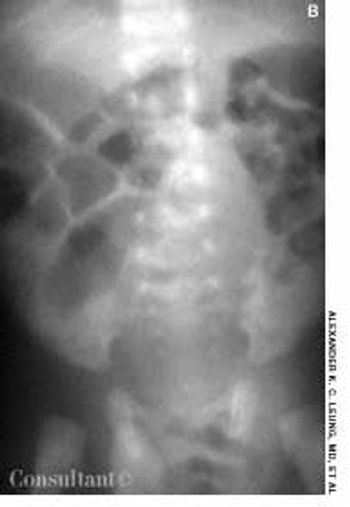

This condition, which accounts for about 30% of cases of intestinal obstruction among neonates, is characterized by the inspissation of thick, tenacious meconium in the bowel. The most common cause is cystic fibrosis; approximately 6% to 20% of infants with cystic fibrosis have meconium ileus. Hyperviscous mucus secreted by abnormal intestinal glands, an abnormal concentrating process in the proximal small intestine, and a deficiency of pancreatic enzymes have been implicated in the pathogenesis. The histologic hallmark is distention of the goblet cells in the intestinal mucosa.